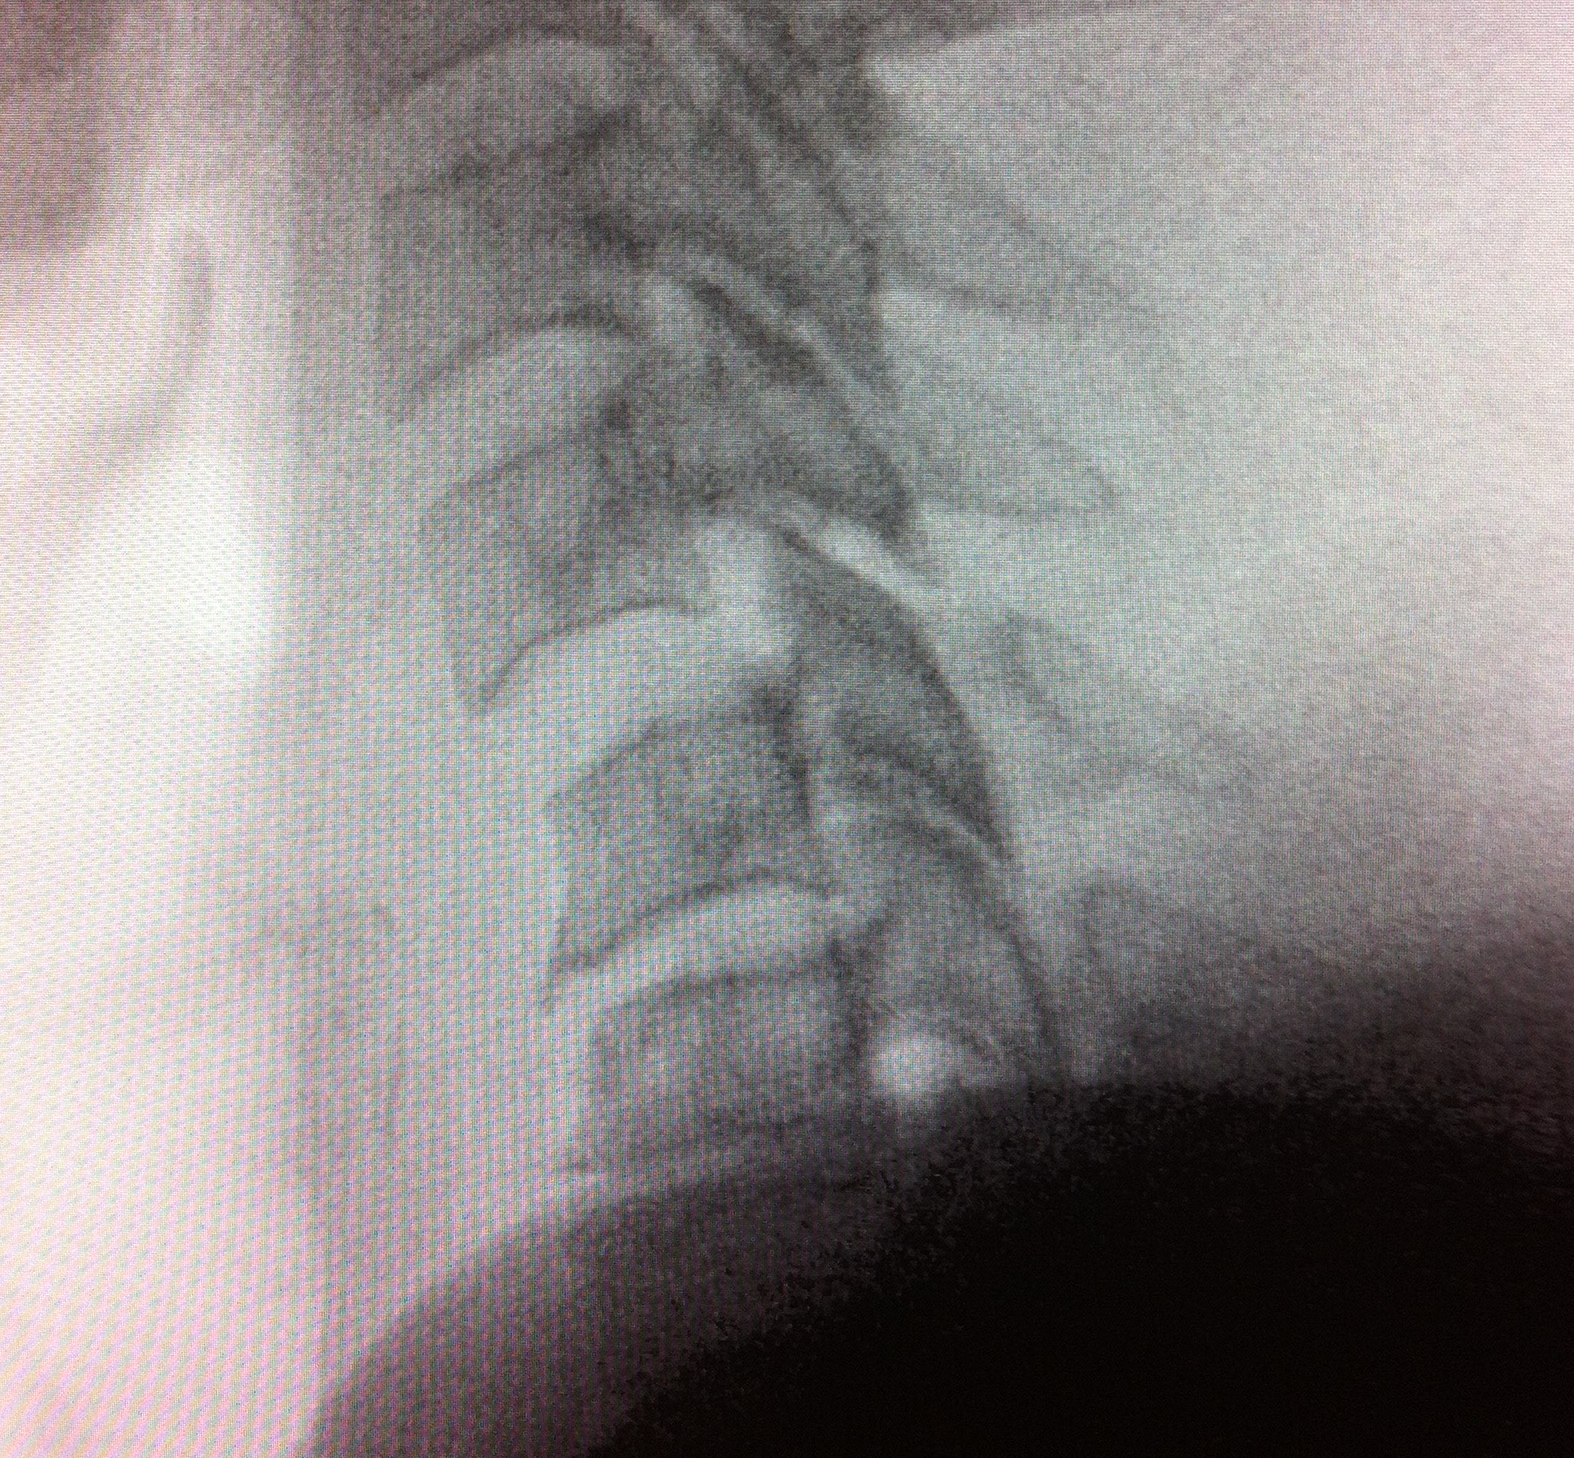

– El TAC reveló el desplazamiento de los cuerpos vertebrales y la compresión medular, lo cual confirmó la severidad de la lesión.